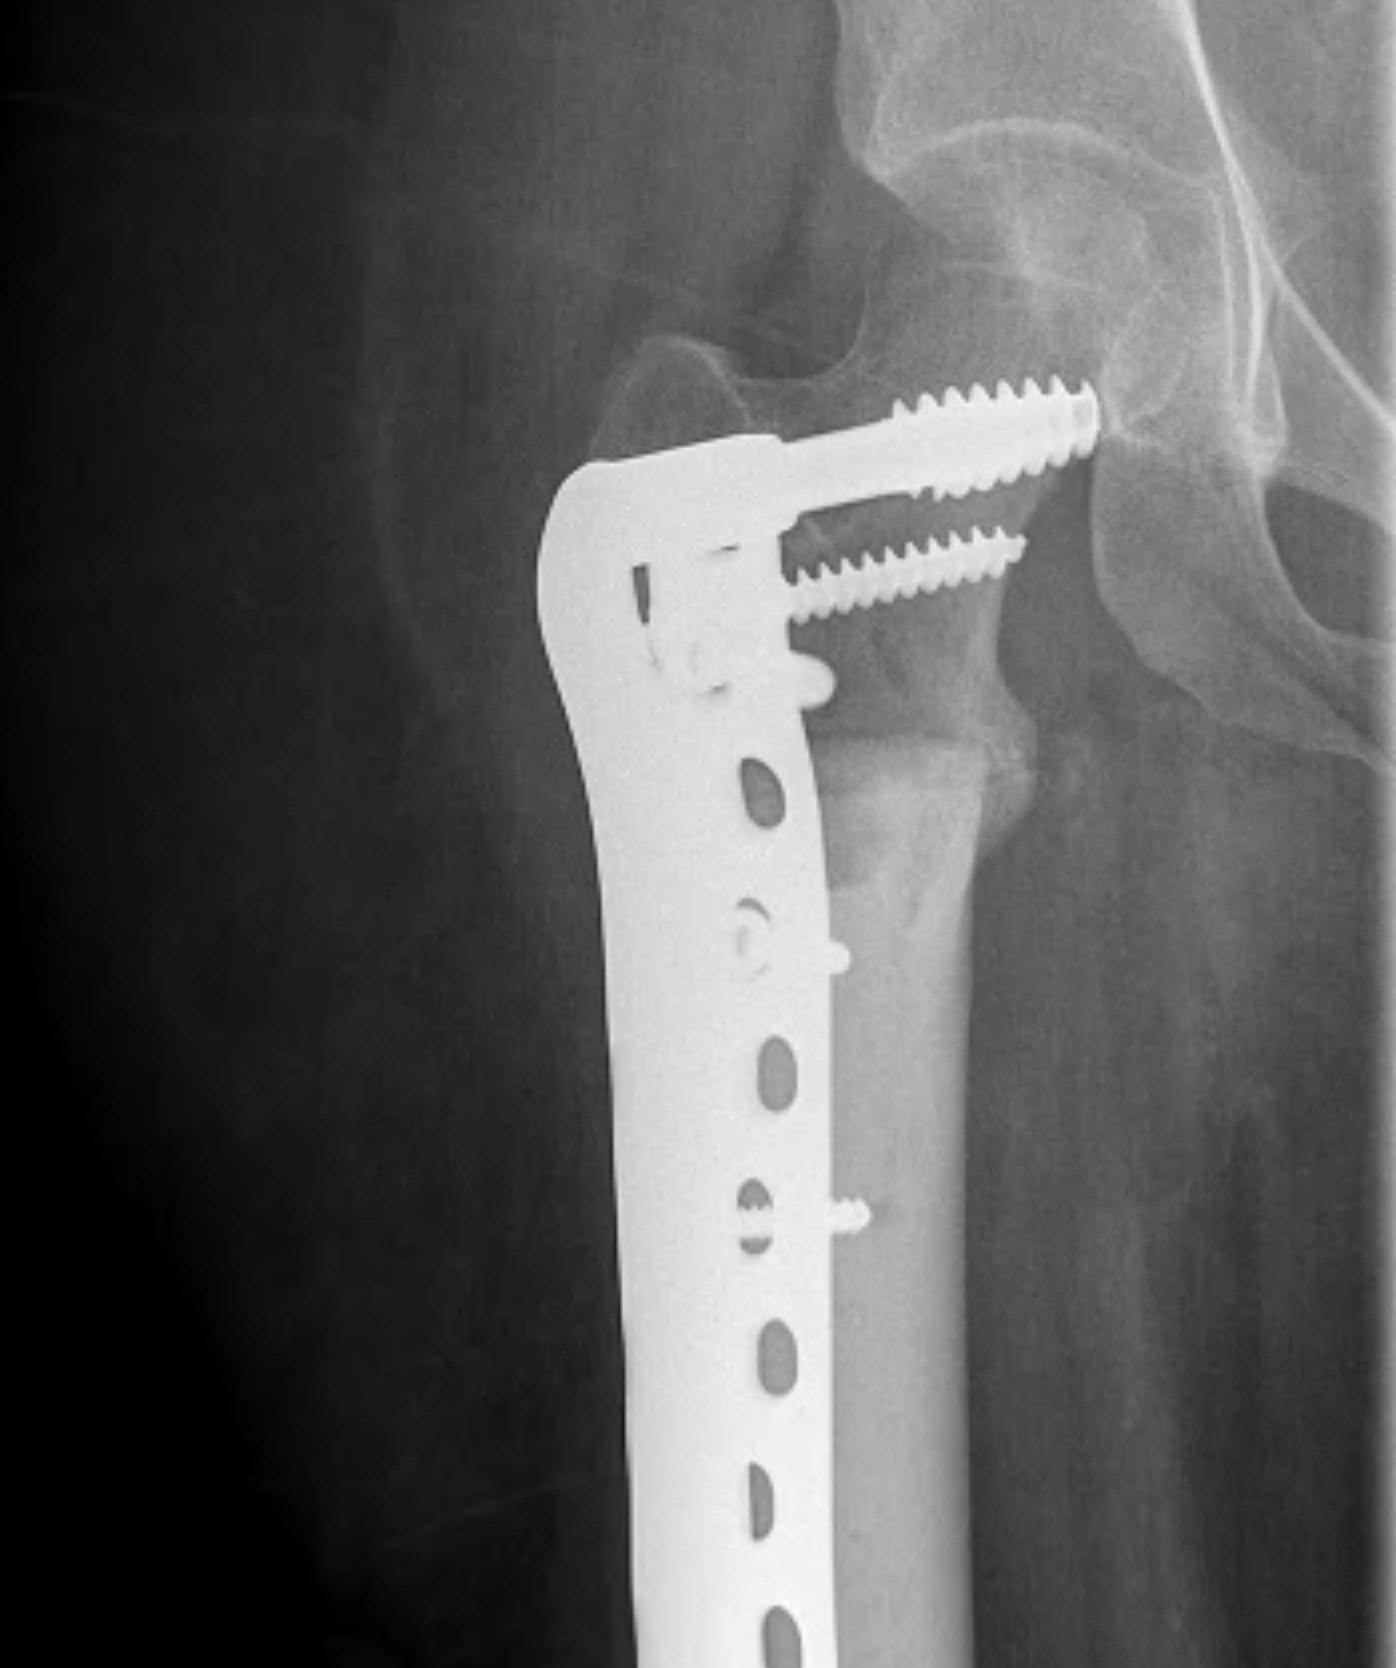

Modular Endoprosthesis

Advantage

Early weight bear and rehabilitation

No risk of non union like allograft

Autograft / Vascularised fibula graft

Advantage over allografts

- more rapid incorporation

- stronger initial construct secondary to graft hypertrophy